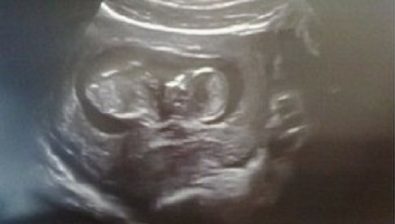

Ultrasound at 12 Weeks

The further along in your pregnancy, the more distinguished your baby’s heartbeat becomes.

At this point, you’re able to hear it by listening with a fetal doppler monitor. Your doctor will likely do this during each prenatal visit.

Your baby’s structures are all formed. From here on out, those structures will be growing at a rapid pace.

You’ll likely be able to see some movement on an ultrasound as your baby is wiggling and moving inside your uterus.

12 Weeks Pregnant: With Twins

On an ultrasound, you might have noticed that one of your babies is slightly bigger than the other.

This is relatively common, so please don’t be alarmed. Your doctor will look into any significant size difference.